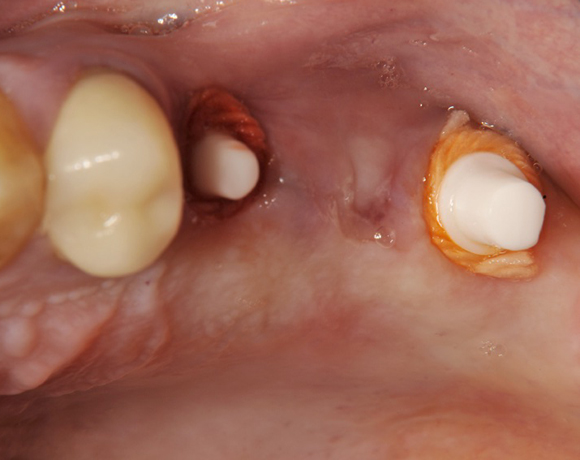

Im vorliegenden Patientenfall wurden für die Zähne 25 und 27 jeweils ein Implantat gesetzt. Nachdem die Implantate eingeheilt waren, wurde 25 – 27 mit einer Brücke versorgt.

Der operative Teil